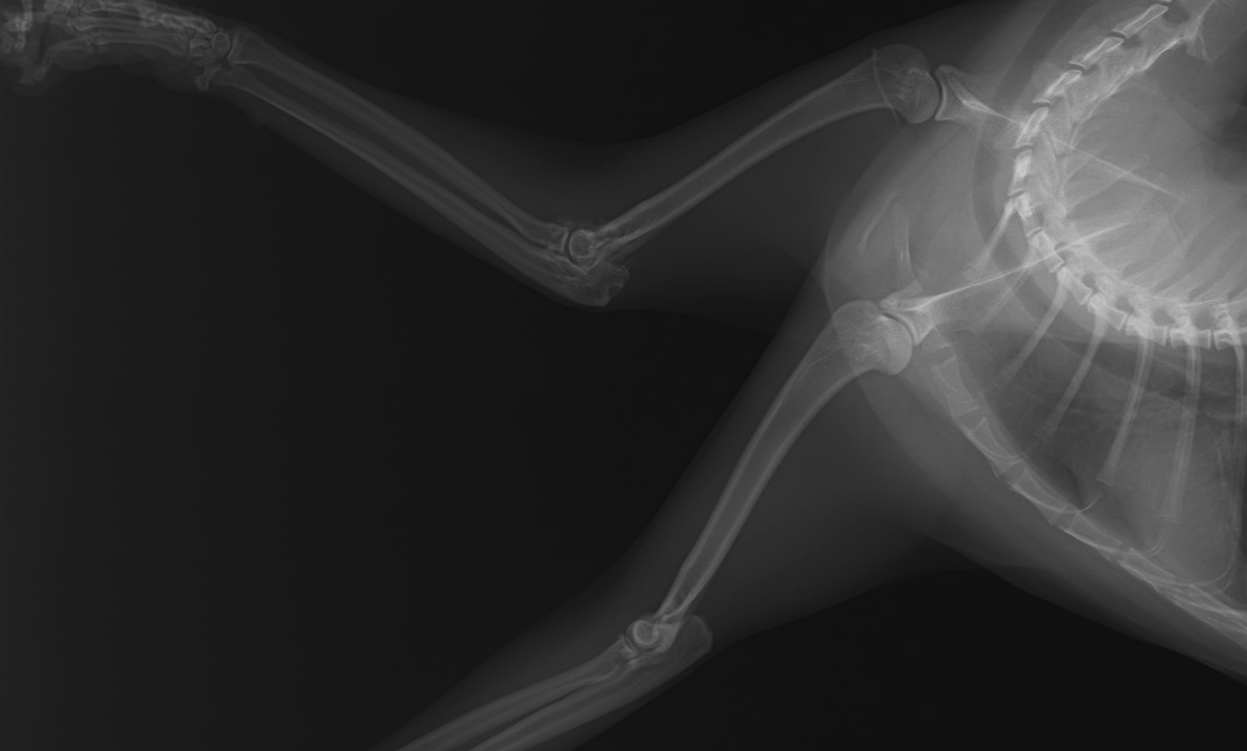

このレントゲン写真は右前脚の痛みがあるという主訴で来院した4歳の猫のものです。上が右前脚、下が左前脚です。拡大するとよくわかるのですが、右の肘関節の周囲がモヤモヤと白く見えているのがわかります(赤矢印)。左肘にはこのような変化は認められません。関節炎が慢性化すると、骨や軟骨の変性が生じ、骨化してレントゲンでも変化が確認できるようになります。レントゲン上は些細な変化ですが、肘関節には大きな異常が生じており、慢性的に痛みを感じるようになります。この子の場合は非ステロイド系鎮痛剤の注射で症状が改善したため、経過観察となっています。